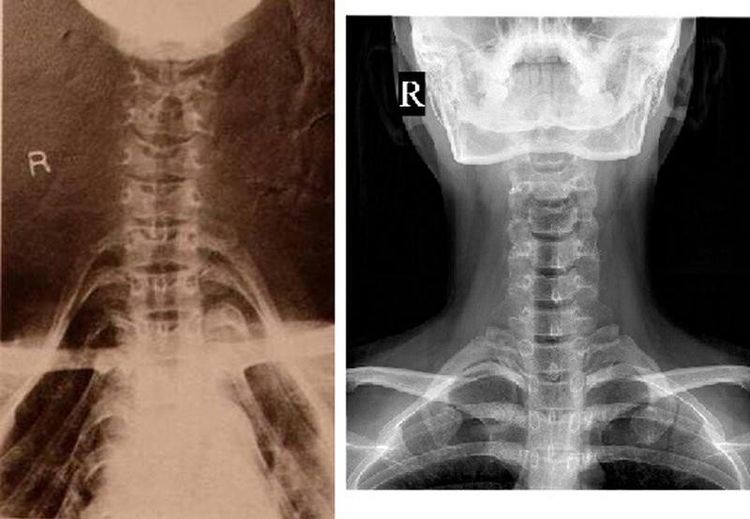

Neck Ring Xray . The image through the lateral part of c2 nicely shows, that the fracture. Normal cervical spine radiographs in a young adult.

The image through the lateral part of c2 nicely shows, that the fracture. Normal cervical spine radiographs in a young adult.